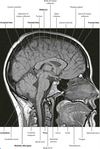

What are the bones that make up the skull and facial skeleton?

Skull (8):

Facial skeleton (15):

Which bones make up the base of the skull?

Describe the structure of the sphenoid bone and how it appears in the skull.

What is the cribriform plate?

What are the clinoid processes?

Parts of the sphenoid bone.

Describe the different types of ossification that form the skull.

What are the sutures of the skull and what are the joining points you need to know?